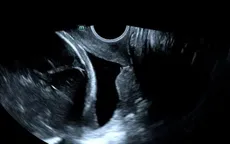

Giữ thai 50 ngày ngoạn mục khi cổ tử cung đã mở 3cm VTV.vn - Sản phụ 30 tuổi đối mặt nguy cơ sinh cực non ở tuần 26 khi cổ tử cung mở 3cm, được khâu cấp cứu và theo dõi sát, kéo dài thai kỳ thêm gần 50 ngày.